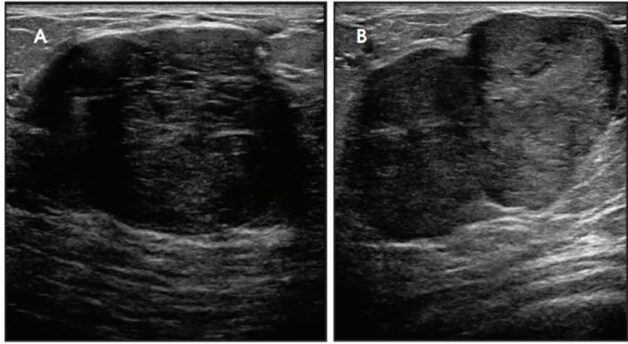

Hình ảnh nhân giảm âm tuyến vú 2 bên